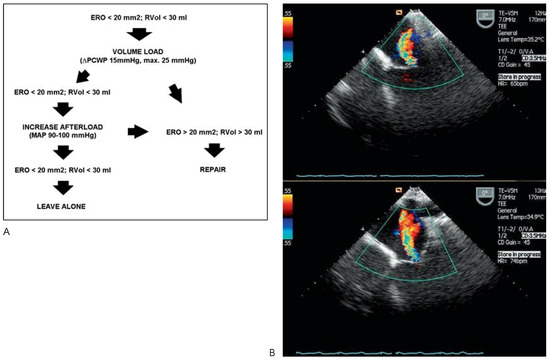

In patients without or insufficient preoperative echoardiographic evaluation an intraoperative loading test may be performed [9,10,11] (Figure 2). Future studies will have to elucidate, how patients with IMR will best be selected for surgical correction. To avoid overlooking an important IMR, all patients scheduled for coronary revascularization, whether it be interventionally or surgically, should undergo TTE assessment. Suspicion should be high in patients with a history of inferoposterior or anterior infarction, impaired LV function (EF <45%), enlarged LV and dyspnea as the leading symptom and IMR aggressively sought after. Assessment of the symmetry of the jet and the tethering is helpful for surgical evaluation and selection of the type of annuloplasty ring [12,13,14].

Figure 2.

(A) Protocol of the intraoperative loading test. Rapid filling to increase preload conditions is performed after aortic cannulation with the aid of the cardiopulmonary bypass machine. (B) Assessment of changes in IMR by transoesophageal echocardiography before (above) and during the loading test (below), showing significant worsening of IMR, indicating the need for surgical correction. ERO = effective regurgitant orifice area; MAP = mean arterial pressure; PCWP = pulmonary capillary wedge pressure; RVol = regurgitant volume.